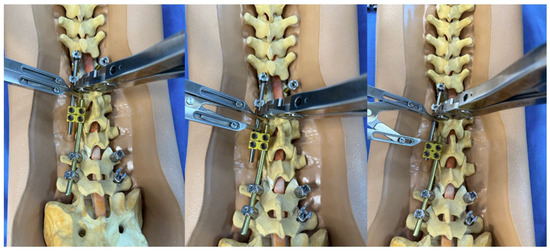

Figure 1.

Sawbone model utilizing a construct-to-construct internal distraction technique showing the greater overlap of the rods across the lateral domino connectors, the more “runway” there is to apply distraction.

Figure 2.

Sawbone model utilizing a construct-to-construct internal compression technique showing reduced overlap of the rods across the lateral domino connectors, the more “runway” there will be to apply compression.